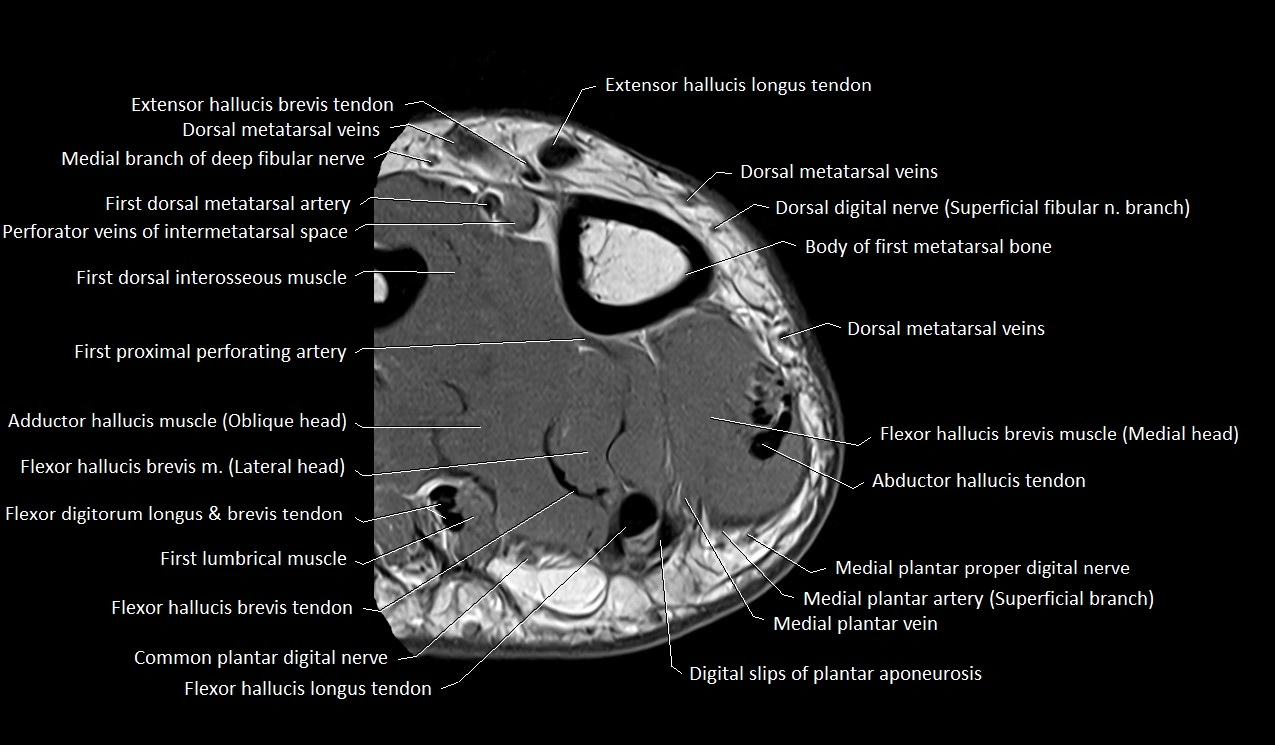

MRI image

image